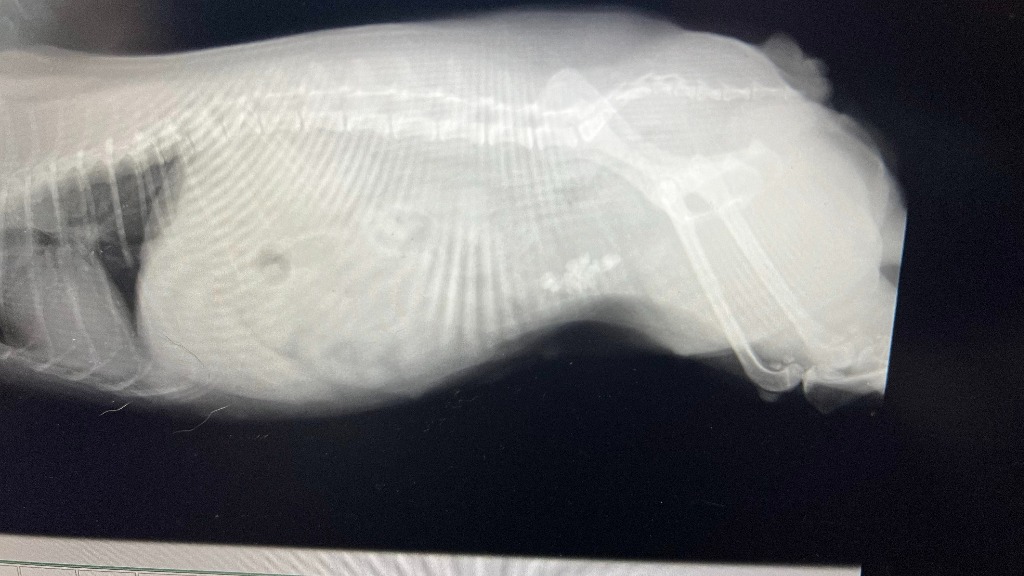

取締役で車監視役のヨークシャーテリアのららの膀胱の結石の摘出手術は、軽井沢の動物病院で受ける事にしました。

取締役で車監視役のヨークシャーテリアのららの体調が良くないので、病院に行ってきました。

血尿が出て元気がありません。

病院で検査してもらったら、膀胱に胆石が沢山できてました。

それによって膀胱内に傷ができて血尿になっていました。

対処法は、手術しかありません。